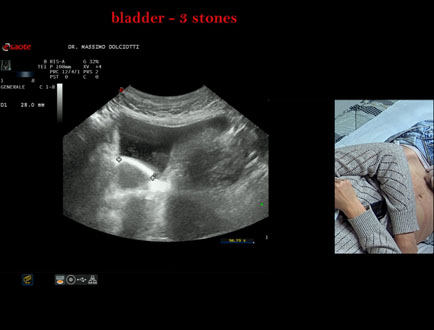

Sonda: Convex Multifrequenza 1-8 MHz

Età Paziente: F 45 anni

Motivazione dell'esame: da alcuni mesi, disuria ed infezioni urinarie recidivanti.

Commento all'esame: le immagini ed il video documentano 3 immagini iperecogene, con cono d'ombra posteriore, da ricondurre a litiasi multipla della vescica.

Conclusioni: 3 calcoli della vescica (3 bladder stones).

Presentazione: Dr. Massimo Dolciotti - Ancona

Elaborazione digitale: Andrea Dini - Ancona

VISUALIZZA IL VIDEO